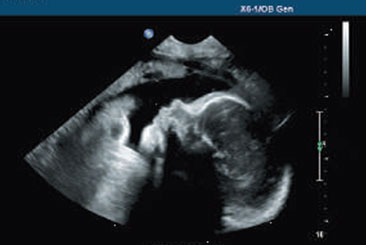

Pregnancy Dating Scans

Pregnancy dating scans, typically done at 6-12 weeks, use ultrasound to determine the due date. They help identify early fetal growth, number of pregnancies, and any potential complications.